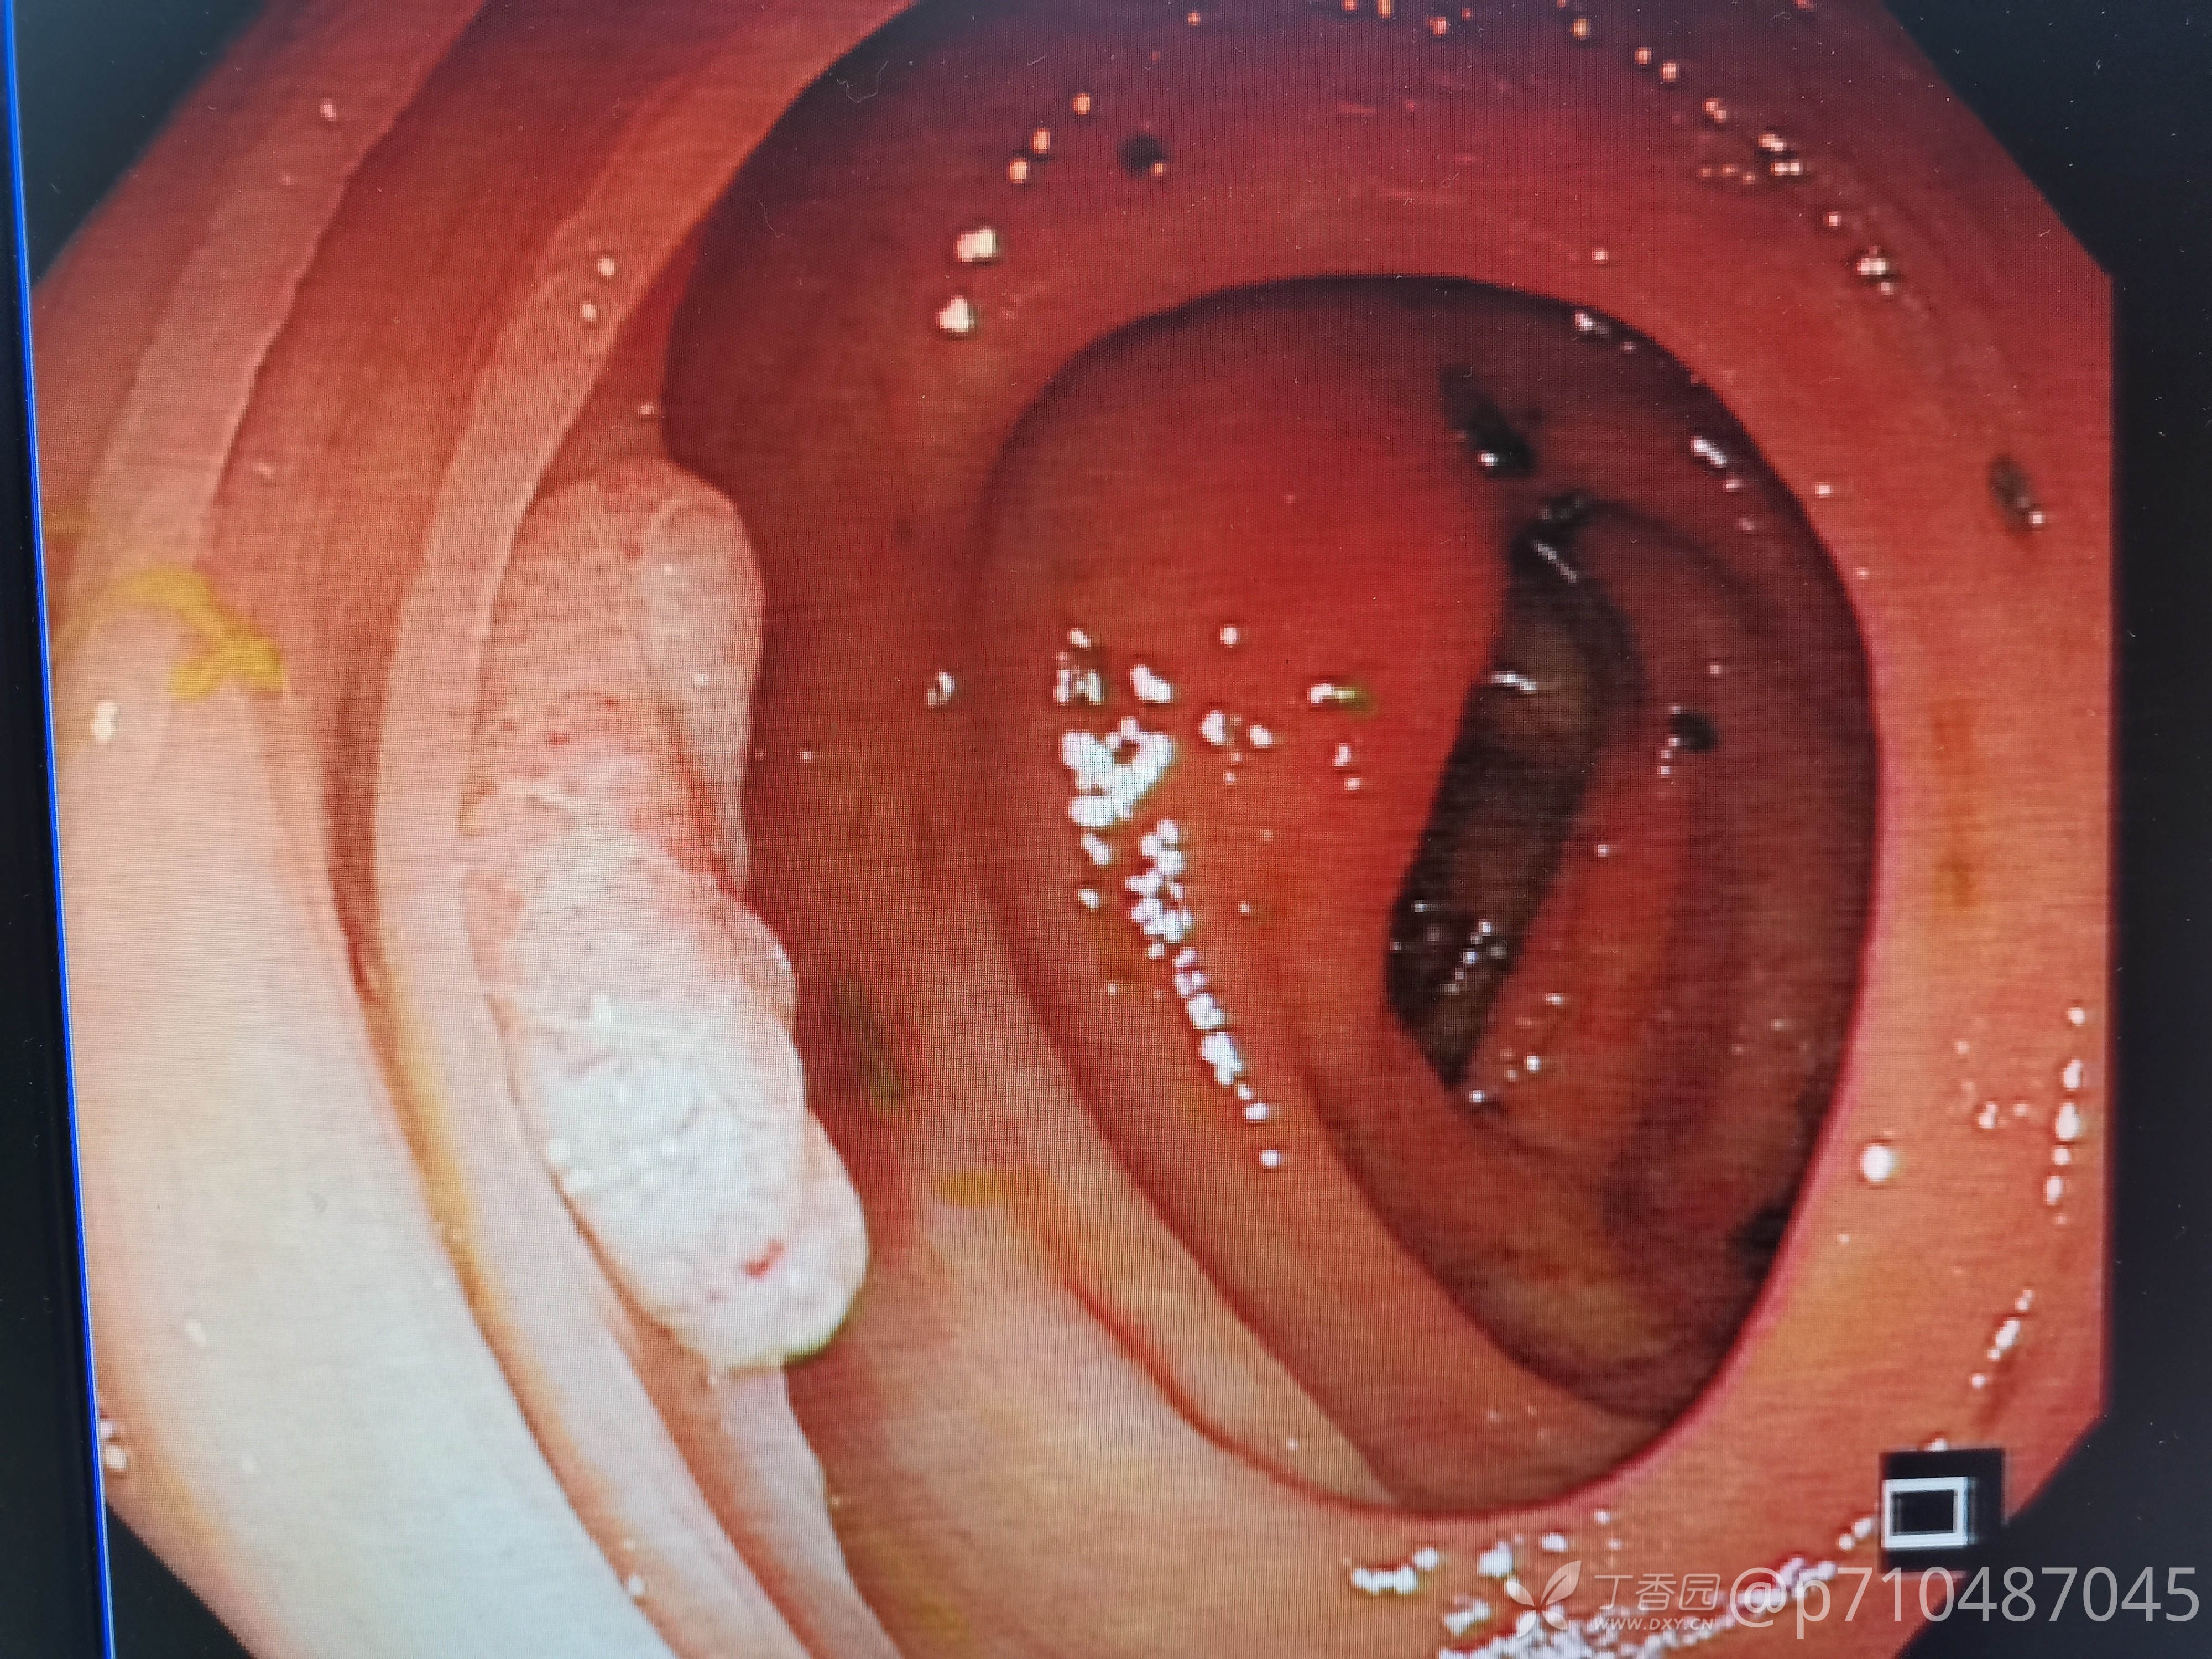

西兰花饺子 推荐第一例病人男性,50岁,第一次行肠镜检查,发现大小息肉5颗,较大者予EMR切除,这么大的第一次切,感觉可以做ESD了😂最后一个夹子打的有点松😳,来回进出几次没发现活动行出血才敢继续退镜。